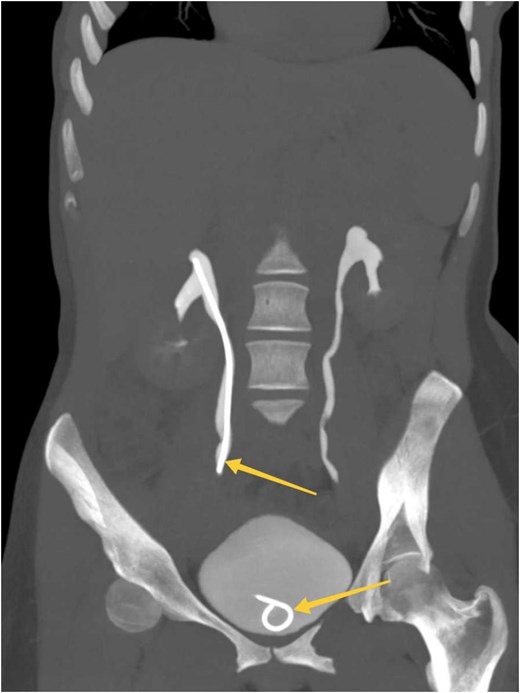

Given the patient's symptoms, an urgent abdominal ultrasound was performed, which demonstrated moderate right-sided hydroureteronephrosis with perinephric-free fluid. Both kidneys appeared normal in size, shape, echostructure, and position. As a result, a contrast-enhanced CT scan of the abdomen and pelvis was performed, revealing an enlarged and edematous right kidney with moderate hydroureteronephrosis. A 3 mm distal ureteric stone was identified ~1.5 cm proximal to the vesicoureteric junction (Fig. 1). Moreover, significant perinephric and periureteral fluid and fat stranding were also noted (Fig. 1). Additionally, there was evidence of partially delayed calyceal contrast excretion with extravasation but no pelvic or ureteric excretion 20 minutes post-contrast injection (Fig. 1). These clinical and imaging findings were highly suggestive of renal calyceal rupture secondary to ureteric obstruction.

(A) Sagittal section of a contrasted CT scan obtained at the venous phase showing moderate right hydronephrosis (arrow) with perinephric free fluid and fat stranding (arrow). (B) MIP reconstructed coronal images of contrasted CT scans obtained at delayed phases showing delayed renal excretion of the right kidney with minimal contrast extravasation out of the pelvicalyceal system (arrows). (C) Axial section of contrasted CT scan showing distal right ureteric stone about 1.5 cm away from vesicoureteric junction (arrow) surrounded by minimal fat stranding and fluid.

Postoperatively, the patient was admitted for monitoring and received intravenous fluids, analgesics, and antibiotics. Her clinical condition improved significantly, and follow-up imaging showed resolution of the obstruction and extravasation (Fig. 2). She was discharged in good clinical condition, with no pain or urinary symptoms. At the one-month follow-up, the D-J stent was removed without complications. The patient reported no recurrence of symptoms, and her clinical outcomes remained good.

MIP reconstructed coronal images of contrasted CT scan obtained at delayed phases (bone window) showing symmetrical bilateral renal excretion with D-J stent in the right ureter and bladder (arrows).